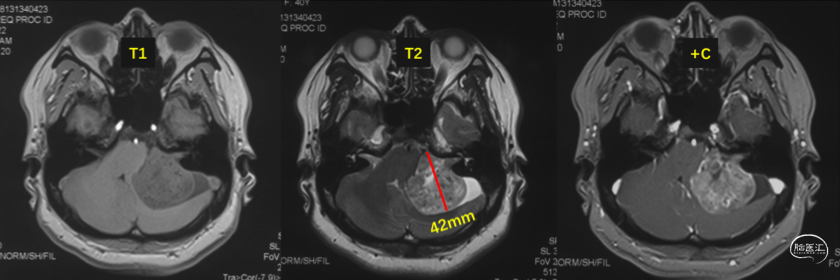

术前影像检查

头颅MRI

肿瘤大小为4.2cmX3.6cm,对于直径大于4cm的巨大听神经瘤而言,肿瘤全切难度大,面瘫发生率高,保留听力更是难上加难。

左侧巨大听神经瘤(4.2cmX3.6cm)